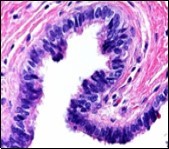

Figure 1.Ciliated cutaneous cyst lined by pseudostratified ciliated columnar epithelium and a supporting fibro-connective tissue stroma 11.

Typically, cutaneous ciliated cyst is a simple cyst which demonstrates a layering of pseudostratified ciliated columnar epithelium recapitulating conventional epithelial lining of the fallopian tube. As the cutaneous ciliated cyst demonstrates a morphological similarity to the fallopian tube lining epithelium, a Mullerian origin is indicated. Gross examination of cutaneous ciliated cyst depicts a solitary, mobile, non-tender, fluctuant, firm or soft to cystic lump with a fibrous wall and abundant amount of circumscribing adipose tissue. Cutaneous ciliated cysts are of a variable dimension. Cut surface usually displays a unilocular cyst impacted with clear, serous fluid, an attenuated smooth, greyish/ white cyst wall incorporated with incomplete septa traversing the cyst 6, 7.

Cutaneous ciliated cyst is layered with a singular layer of ciliated epithelial cells which are chiefly constituted by cuboidal to columnar epithelium, traversed by partially configured fibrous tissue septa with an admixture of randomly dispersed, intraluminal papillary projections akin to those cogitated in the fallopian tube. Superimposed epithelium is inundated with well vascularized, parallel bundles of collagen although smooth muscle is absent 7, 8.